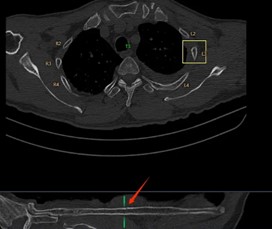

在一些大型醫(yī)院和醫(yī)療研究機(jī)構(gòu),已經(jīng)開始嘗試這種協(xié)作模式。例如,在胸部CT肺結(jié)節(jié)以及肋骨骨折的影像診斷中,AI 首先對(duì)影像進(jìn)行分析,標(biāo)記出可能的異常區(qū)域,醫(yī)生再對(duì)這些區(qū)域進(jìn)行詳細(xì)觀察和診斷。通過這種協(xié)作,不僅提高了診斷效率,還提升了診斷的準(zhǔn)確性。